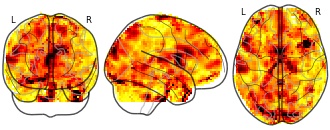

"name": "Multi_VBMsmaller_fMRIenhanced",

"description": "Multi-modal analysis in BPD. Brain regions exhibiting smaller gray matter and enhanced activation during emotion processing in BPD compared to healthy controls. Note: Results were thresholded at p<.0025. Note2: Results were updated (see Erratum for this publication).",